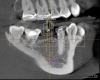

Fig. 1 and Fig. 2 In x-ray imaging, a 2D view creates superimposition and can lead to distortion of the distance between structures; 3D imaging uses a cone-shaped beam and captures the entire area being imaged in a single rotation.

Figure 1

For more than 100 years, two-dimensional radiographic imaging has been a standard diagnostic tool in dentistry despite the inherent limitation of viewing a three-dimensional (3D) object in two dimensions (2D). A two-dimensional view creates superimposition and distortion of the distance between structures (Figure 1 and Figure 2). In the 1970s, computerized axial tomography, or CAT scans, became available for 3D imaging but had limited use in dentistry because of high radiation dosages, cost, and accessibility issues. With the commercial introduction of cone-beam computed tomography (CBCT) in 2001, dentists have found it practical to perform 3D imaging in the dental office and it has been increasing in use.1 In 2003, Hashimoto et al reported that the one CBCT unit produced better image quality with a much lower radiation dose than the newest multidetector-row helical CT unit (1.19 mSv vs 458 mSv per examination).2